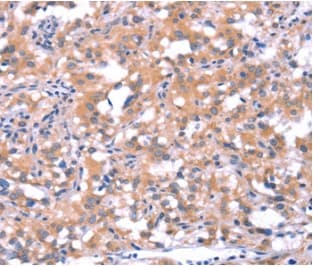

Anti-FAT/FAT1 antibody(AB198892)

Rabbit Polyclonal FAT/FAT1 antibody. Suitable for IHC-P and reacts with Human samples. Cited in 2 publications. Immunogen corresponding to Synthetic Peptide within Human Protocadherin Fat 1.